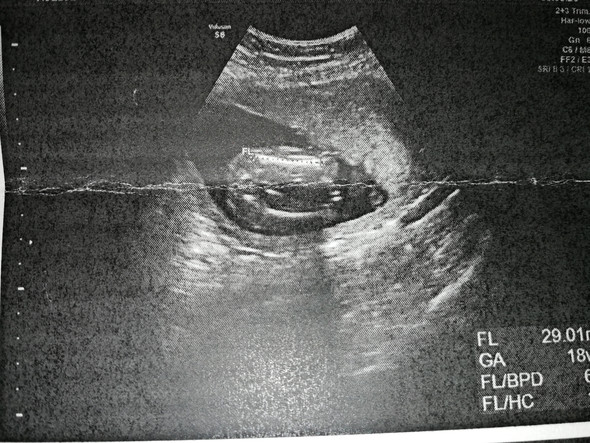

Donnerstag stand nun also ein wichtiger Frauenarzttermin an, den ich mir auf keinen Fall entgehen lassen wollte Schließlich ist meine Verlobte jetzt in der 18SSW und wir sind neugierig, ob wir beim Ultraschall das Geschlecht erkennen könnenDas heißt, unser heutiger Termin ist mit einer UltraschallUntersuchung verbunden (Ich muss dazu sagen, dass unser Gynäkologe Herr Schrey ein super. Mit der 18SSW sind Sie bereits im fünften Monat schwanger – und vielleicht macht sich Ihr Baby schon jetzt zum ersten Mal mit leichtem Bauchprickeln bemerkbar Lesen Sie hier, was sich in der 18 SSW außerdem tut, zum Beispiel, warum Bewegung jetzt nicht nur Sie entspannt und warum Sie Blutungen immer ernst nehmen müssen. Größe Dein Baby ist in der 18 SSW ungefähr so groß wie eine Süßkartoffel (1314 cm ScheitelSteißLänge) Gewicht Der Fötus wiegt in der 18 Schwangerschaftswoche zwischen 150 und 0 Gramm Noch 22 Wochen bis zur Geburt!.

Was bedeutet 18 SSW?. Hallo ich war letztesmal in der 12 ssw beim ultraschall, und vor kurzem wieder bei der 21ssw das baby ist schon gewachsen, aber viiiiel viiiel grösser ist es jetzt nicht. Donnerstag stand nun also ein wichtiger Frauenarzttermin an, den ich mir auf keinen Fall entgehen lassen wollte Schließlich ist meine Verlobte jetzt in der 18SSW und wir sind neugierig, ob wir beim Ultraschall das Geschlecht erkennen könnenDas heißt, unser heutiger Termin ist mit einer UltraschallUntersuchung verbunden (Ich muss dazu sagen, dass unser Gynäkologe Herr Schrey ein super.

Ihr Baby in SSW 33 43,7 cm 1918 Gramm Ihr Baby in SSW 34 45,0 cm 2146 Gramm Ihr Baby in SSW 35 46,2 cm 23 Gramm Ihr Baby in SSW 36 47,4 cm 2622 Gramm Ihr Baby in SSW 37 48,6 cm 2859 Gramm Ihr Baby in SSW 38 49,8 cm 30 Gramm Ihr Baby in SSW 39 50,7 cm 32 Gramm Ihr Baby in SSW 40 51,2 cm 3462 Gramm Ihr Baby in SSW 41. SSW 18 Spürt das Baby den Ultraschall?. 4D Video Ultraschall 18 SSW, wwwdostalgynde.